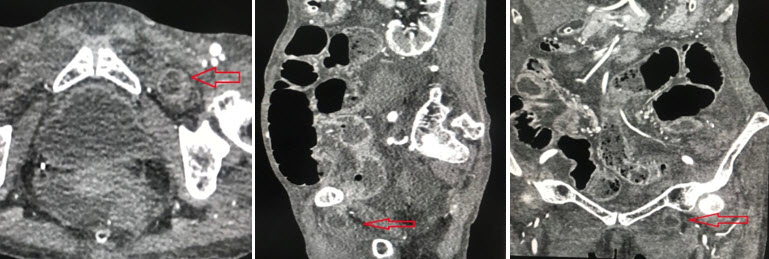

Chụp cắt lớp vi tính ổ bụng: các quai ruột non giãn kèm mức hơi dịch (h/a tắc ruột ). Hình ảnh quai ruột non chui qua lổ bịt trái. Dịch tư do ổ bụng lượng vừa. Tràn dịch màng phổi 2 bên lượng ít. (Hình 3).

Hình 3. Hình ảnh CT scan của thoát vị đùi- Mũi tên đỏ là quai ruột thoát vị

Chụp CT scan đa lát cắt trong cấp cứu có thể nhanh chóng chẩn đoán và can thiệp phẫu thuật sớm đối với các trường hợp thoát vị bịt do đó nâng cao được kết quả điều trị. Sử dụng CT scan trong chẩn đoán thoát vị bịt được báo cáo lần đầu tiên bởi Meziane và cộng sự vào năm 1983 [5].  Dấu hiệu trên CT scan hay gặp là quai ruột chui qua lỗ bịt nằm giữa cơ lược và cơ bịt ngoài.

Hình 5: CTscan mặt phẳng axial cho thấy 1 quai ruột non trong túi thoát vị (hình ngôi sao trắng), ngoài cơ bịt ngoài (mũi tên vàng), trong cơ lược (mũi tên đỏ). Mũi tên xanh chỉ cơ bịt trong. * Nguồn: theo Sotiropoulos G.C (2013) [6]

Các dấu hiệu khác trên CT scan: các quai ruột non giãn, có hình mức dịch-khí, điểm chuyển tiếp ở lỗ bịt  Nếu chẩn đoán muộn có thể thấy các biến chứng thiếu máu, hoại tử hoặc thủng quai ruột. Có thể thấy dịch tự do ổ bụng, giữa các quai ruột, khí ổ bụng (trường hợp có biến chứng). Sử dụng CT scan giúp chúng ta có thể chẩn đoán thoát vị bịt trước mổ 43%-90% các trường hợp [4]. CT scan có thể chẩn đoán chính xác không chỉ thoát vị bịt mà còn chẩn đoán chính xác các tình trạng tắc ruột khác. Giải phẫu vùng thấp của tiểu khung nơi có lỗ bịt được bộc lộ rất tốt trên CT scan có độ phân giải cao. CT scan đa dãy với tái tạo đa bình diện cho các chi tiết giải phẫu chính xác, phân biệt thoát vị với các khối khác [u, tụ máu, áp xe]